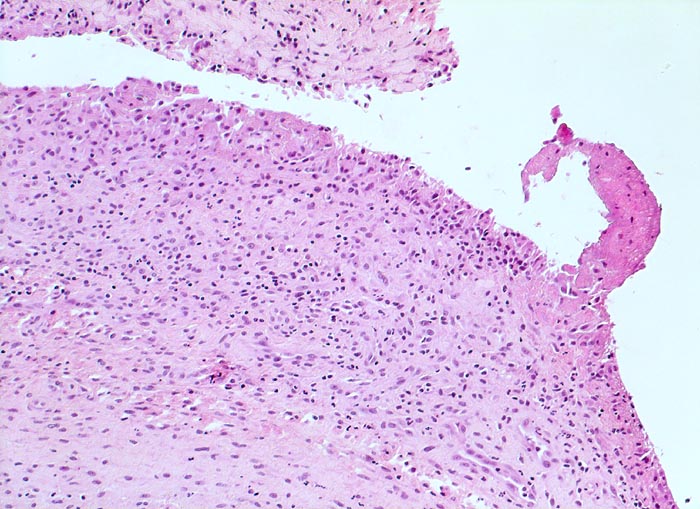

PathoPic ID 4775 - Synovialitis bei chronischer Polyarthritis

Synovialitis bei chronischer Polyarthritis

Systemerkrankung/Immunpathologie

Synovialis

Knochen, Knorpel, Gelenke

Verdickte synoviale

Deckzellschicht. Lockeres gemischtes Entzündungsinfiltrat im Stroma. Fokale

Fibrinauflagerungen.

Bekannte seropositive chronische Polyarthritis.

Histologie

100